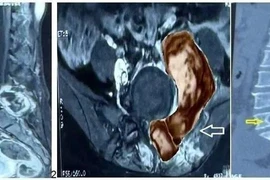

Đau lưng, cô gái 26 tuổi bị u nang tuyến thượng thận khổng lồ, hiếm gặp

U nang tuyến thượng thận là một bệnh lý hiếm gặp, có thể biến chứng nguy hiểm đến sức khỏe, tính mạng của người bệnh.